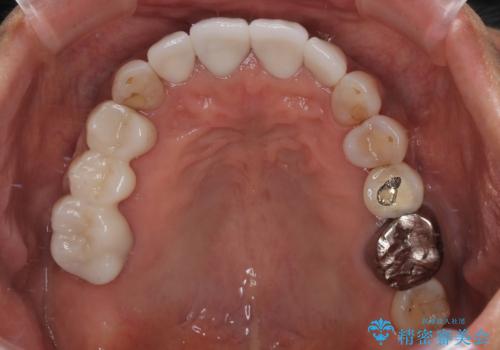

- 矮小歯である前歯がしみるとのことで来院された患者様です。

上顎前歯の歯肉ラインにエナメル質の欠損が認められ、そこが原因で冷たいものがしみている状態でした。

歯の大きさが小さいこと、隣の歯や反対側のセラミッククラウンの境目が見えていることなどから、前歯4本あるいは6本に対して、オールセラミッククラウンによる補綴治療をご提案しました。

見た目も大事だが、なるべく削りたくないとのことで、取り急ぎ4本を補綴治療し、今後犬歯の色などが気になることがあれば、追って対応することとしました。

6本同時に処置を行うと、矮小歯をより大きく見えるように工夫ができるというメリットがありましたが、4本のみの処置でも十分に満足をされていらっしゃいました。